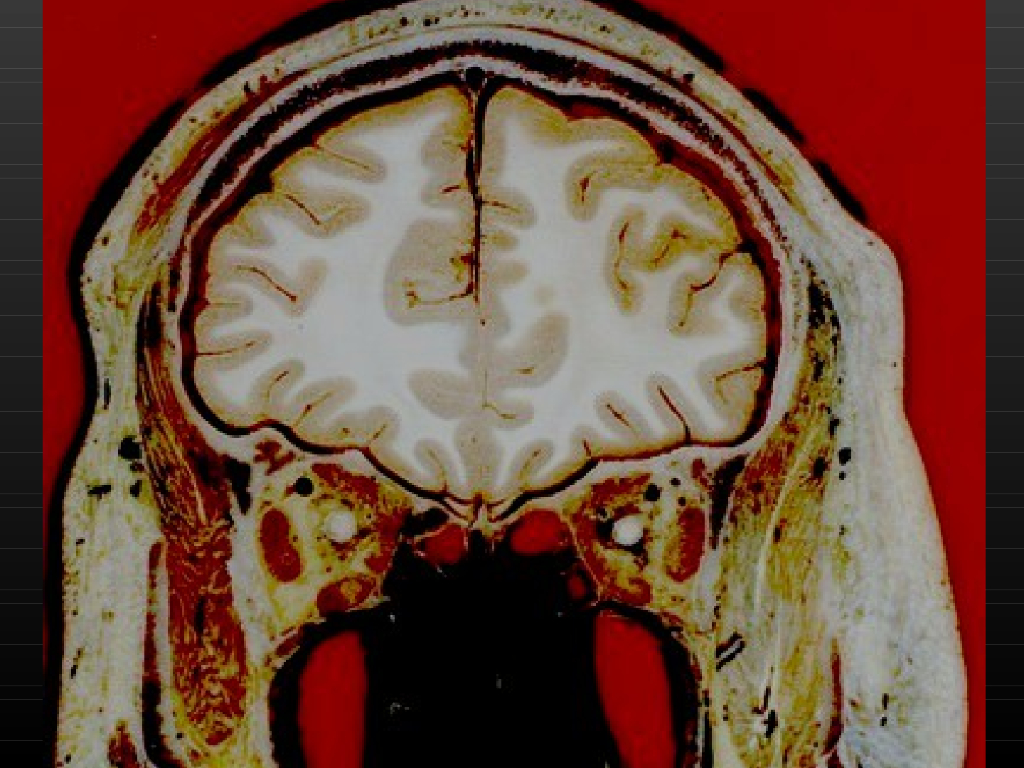

《断层影像解剖学》演示文稿-头部冠状断层解剖与MRI.pdf